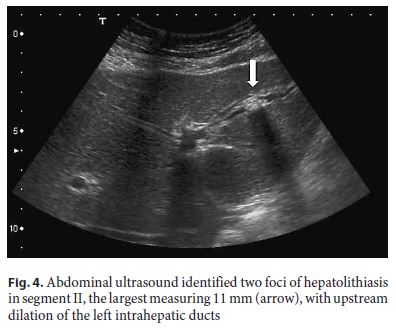

Repeated abdominal ultrasound identified two foci of hepatolithiasis in segment II, the largest measuring 11 mm, with upstream dilation of the left intrahepatic ducts, with no underlying stricture (Fig. 4). Although these had not been identified in MRCP on presentation, we note that left intrahepatic dilation was already visible then.